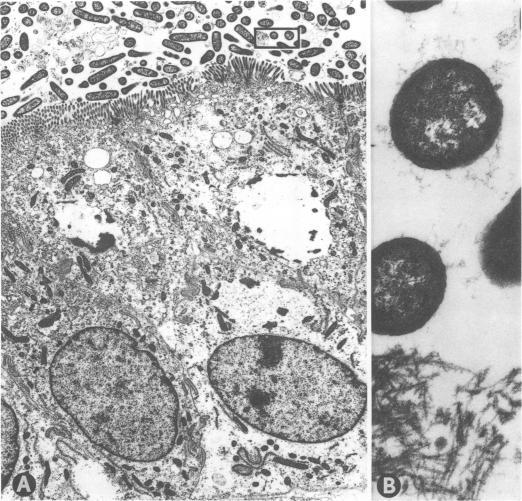

Three strains of enterotoxigenic Escherichia coli which adhered, colonized intensively, and caused disease in pig intestine, but which did not produce pili of the K88, K99, or 987P antigen types were designated 3P(-) ETEC. The 3P(-) ETEC caused mannose-resistant hemagglutination, adhered to porcine intestinal epithelial cells in vitro, and produced pili. However, most bacteria taken directly from the intestine of pigs infected with 3P(-) ETEC appeared to be nonpiliated. Two preparations were isolated from the 3P(-) ETEC. One (material A) contained pili, caused mannose-sensitive hemagglutination, and did not inhibit adhesion of whole bacteria to epithelial cells in vitro. The other (material B) had no demonstrable pili, caused mannose-resistant hemagglutination, and blocked ahesion of bacteria to epithelial cells in vitro. Antiserum against an acapsular mutant (K(-)) of one 3P(-) ETEC strain was absorbed to remove antibodies directed against somatic (O) antigen. The absorbed antiserum agglutinated all three 3P(-) ETEC strains grown in the K(-) form at 37 degrees C, but not when they were grown at 18 degrees C. The absorbed antiserum blocked the hemagglutinating activity of material B, but not of material A. It also reacted (via indirect immunofluorescence) with all of the 3P(-) ETEC when they were grown in pig intestine. The results were interpreted to indicate that: (i) the epithelial adhesive and mannose-resistant hemagglutinating activities of the 3P(-) ETEC strains may be mediated by an antigen contained in material B; (ii) this antigen either is not pilus associated or is associated with pili that are not demonstrable by the methods used here; (iii) the 3P(-) ETEC strains produce type 1 pili which do not mediate their adhesion to intestinal epithelium of pigs.

三株产肠毒素大肠杆菌在猪肠道内黏附、大量定植并致病,但不产生K88、K99或987P抗原类型的菌毛,被命名为3P(-) ETEC。3P(-) ETEC引起甘露糖抗性血凝反应,能在体外黏附猪肠道上皮细胞并产生菌毛。然而,直接从感染3P(-) ETEC的猪肠道中获取的大多数细菌似乎没有菌毛。从3P(-) ETEC中分离出两种制剂。一种(物质A)含有菌毛,引起甘露糖敏感血凝反应,且在体外不抑制全菌对上皮细胞的黏附。另一种(物质B)未检测到菌毛,引起甘露糖抗性血凝反应,并在体外阻断细菌对上皮细胞的黏附。用一株3P(-) ETEC菌株的无荚膜突变体(K(-))制备的抗血清经吸收以去除针对体细胞(O)抗原的抗体。吸收后的抗血清能凝集在37℃以K(-)形式生长的所有三株3P(-) ETEC菌株,但不能凝集在18℃生长的菌株。吸收后的抗血清阻断了物质B的血凝活性,但未阻断物质A的血凝活性。它还(通过间接免疫荧光法)与在猪肠道中生长的所有3P(-) ETEC发生反应。结果表明:(i)3P(-) ETEC菌株的上皮黏附及甘露糖抗性血凝活性可能由物质B中所含的一种抗原介导;(ii)该抗原要么与菌毛无关,要么与用此处所用方法无法检测到的菌毛相关;(iii)3P(-) ETEC菌株产生1型菌毛,但这些菌毛并不介导其对猪肠道上皮细胞的黏附。